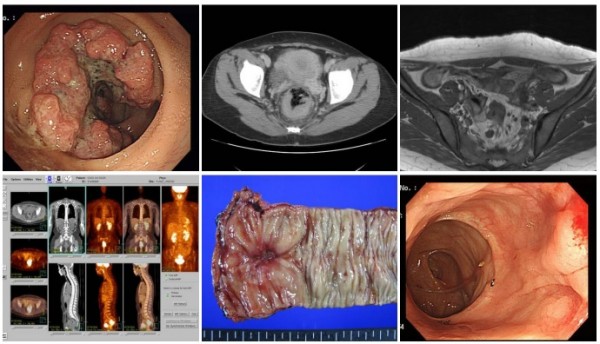

대장암, 걱정말아요 그대

대장암은 결장암과 직장암으로 구분하는데 치료하는 방법에는 크게 수술요법, 항암화학요법, 방사선요법, 표적치료, 면역요법 등이 있으며 이들 방법은 단독 혹은 병합되어 사용되고 있으며 아직까지는 수술로서 암을 완전히 제거해주는 것이 가장 효과적인 치료법으로 인정되고 있으며, 방사선 요법 및 항암화학요법과 표적치료는 주로 보조적이거나 전이암에 대한 치료수단으로 사용되고 있다.

대장암은 결장암과 직장암으로 구분하는데 치료하는 방법에는 크게 수술요법, 항암화학요법, 방사선요법, 표적치료, 면역요법 등이 있으며 이들 방법은 단독 혹은 병합되어 사용되고 있으며 아직까지는 수술로서 암을 완전히 제거해주는 것이 가장 효과 적인 치료법으로 인정되고 있으며, 방사선 요법 및 항암화학요 법과 표적치료는 주로 보조적이거나 전이암에 대한 치료수단으로 사용되고 있다.

최근 들어 외과적 수술 수기의 발달, 적극적인 수술방법의 도입, 수술 전 처치의 발달 등으로 수술을 통한 대장암의 절제 가능성이 증가하였고, 수술에 따른 합병증이 감소하였고, 또한 조기 발견에 의한 근치수술로 대장암의 완치가 가능하기 때문에 외과적 수술요법은 대장암의 치료에 있어서 중추적인 역할을 하고 있다.

더욱이 내시경 술기의 발달과 더불어 대장암의 선행단계인 선종이 제거되고 조기 대장암의 내시경적인 절제도 늘어서 조기발견의 중요성과 정기검진이 필요하게 되었다.